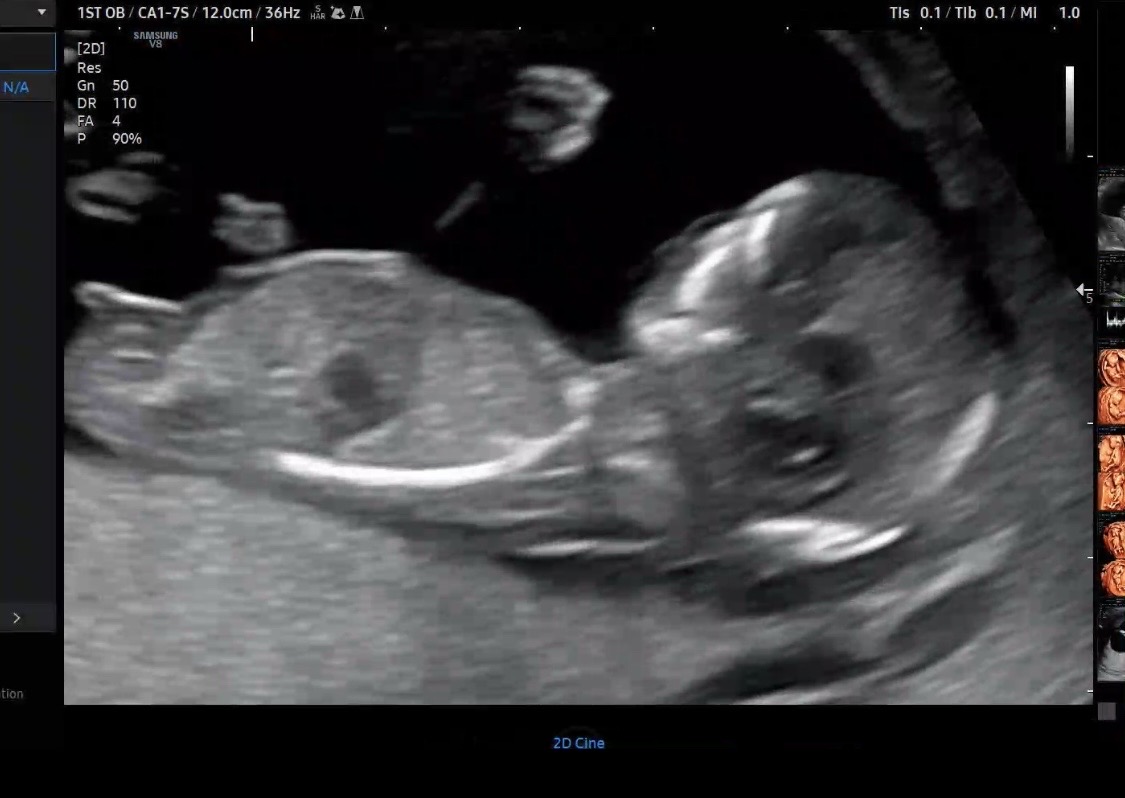

12주5일 각도법 봐주세요ㅠㅠ

성별 대충이라도 예측할 수 있을까요? 전문가님들 투표 부탁드려요~